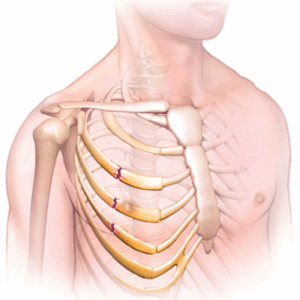

Broken ribs

A broken rib is a common injury that occurs when one of the bones in the rib cage breaks or cracks. The most common causes are hard impacts from falls, car accidents or contact sports.